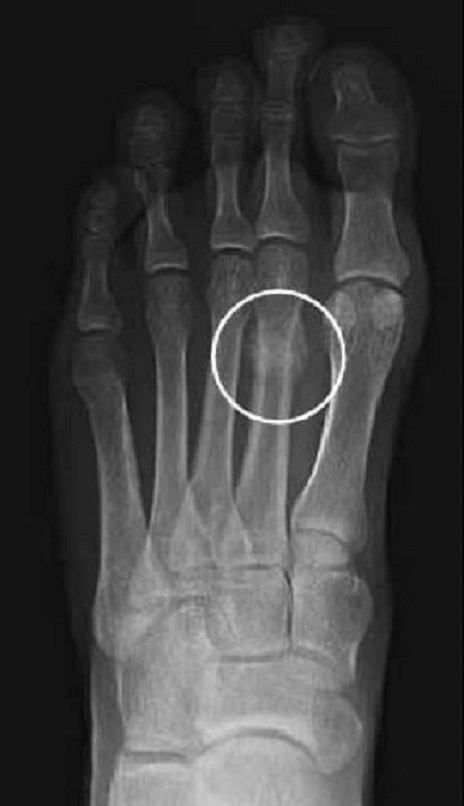

طبق اعلام تیم پزشکی مادریدیها، شوامنی پس از الکلاسیکو از ناحیه استخوان متاتارس دوم انگشت پای چپش دچار شکستگی شده و هرچند زمان دقیقی برای بازگشت او اعلام نشده، ولی طبق ادعای رسانههای اسپانیایی، چنین مصدومیتی دو ماه ریکاوری نیاز دارد.